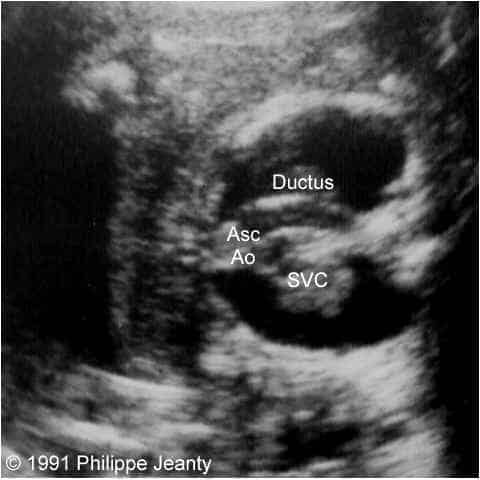

A 42-year-old G5P4 patient, whose pregnancy was uncomplicated until the 21st week of gestation when a discrepancy between size and dates was noted, was referred for a level II scan. The examination demonstrated significant polyhydramnios. The biometry was consistent with 23 weeks, and an edematous fetus with pleural effusions was found. A complex cardiac anomaly was noted (fig. 1).

Figure 1: Top (left & right): Axial views of the base of the heart. The relationship between the superior vena cava (SVC), the ascending aorta (asc Ao) and the ductus is seen. Notice the larger size of the ductus compared to the aorta. Middle left: This section, just cephalad to the two previous, demonstrates the common carotids and the SVC. Middle right: Longitudinal section. The SVC is seen entering the right atrium (RA). The ascending aorta is between the SVC and the ductus. It does not connect with the ductus, and bifurcates into the common carotids. Bottom left: Similar view to the previous one. The conection between the ductus and the right ventricle (RV) is demonstrated. The ascending aorta lacks its normal curve towards the back and the left of the fetus. Bottom right: Thickened neck tissue with small cystic hygroma. Note the posterior nuchal ligament in the cyst.

The heart had four chambers, with its apex on the left. Large ventricular and atrial septal defects were present. The systemic venous circulation could be traced to the right atrium, entering the right ventricle, then following through the ductus arteriosus into the descending aorta. On the left side, one vessel could be traced cephalad from the ascending aorta from which both common carotid arteries originated. There was no communication between the ascending and descending aorta.